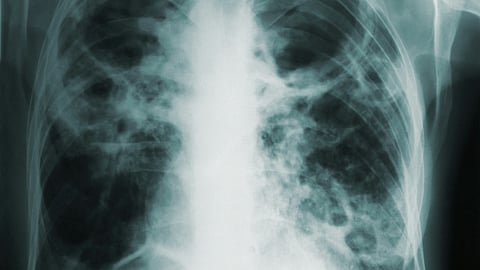

Active TB disease is when TB bacteria multiply and can cause symptoms like cough, night sweats, fever and weight loss. Skin or blood tests will likely be positive and radiography (e.g., chest X-ray or CT scan) will be abnormal.